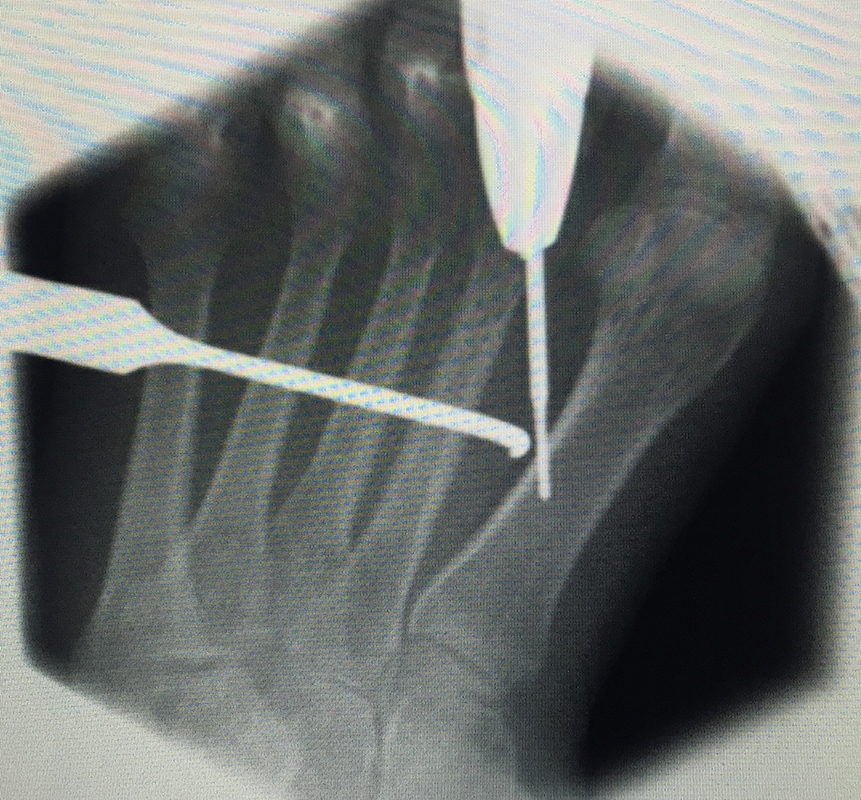

In der minimalinvasiven Fußchirurgie ist es unabdingbar, die Fräse in ihrer Position zum Knochen radiologisch zu kontrollieren, damit vulnerable Wachstumsfugen oder angrenzende Gelenke nicht verletzt werden. Zu diesem Zweck werden mit einem Bildwandler während der Operation die genaue Position der Fräse und der Osteotomieverlauf überprüft, was die Strahlenbelastung im Vergleich zu offenen Verfahren erhöht. Diese Strahlenbelastung hat potenziell einen schädigenden Einfluss auf den noch blutbildenden Knochen von Heranwachsenden. Gesicherte Landmarken am Fuß können die notwendige Zahl der Röntgenbilder und damit die Strahlung minimieren. Ist es erforderlich, mehrere Knochen zu osteotomieren, wie zum Beispiel im Bereich der Kleinzehen, werden anhand der Landmarken kleine Injektionsnadeln auf Höhe der geplanten Osteotomien vorgelegt und radiologisch im Bildwandler (BV) dokumentiert (Abb. 11). Ein solches Bild schafft eine gute Orientierung, sodass auf radiologische Kontrollen intraoperativ weitestgehend verzichtet werden kann.

Abb. 11: Lokalisation mehrerer Stichinzisionen mit einem Röntgenbild.

Zum Lesen der Bildbeschreibung und zur Vollansicht bitte das Bild anklicken. Bild: A. Helmers.